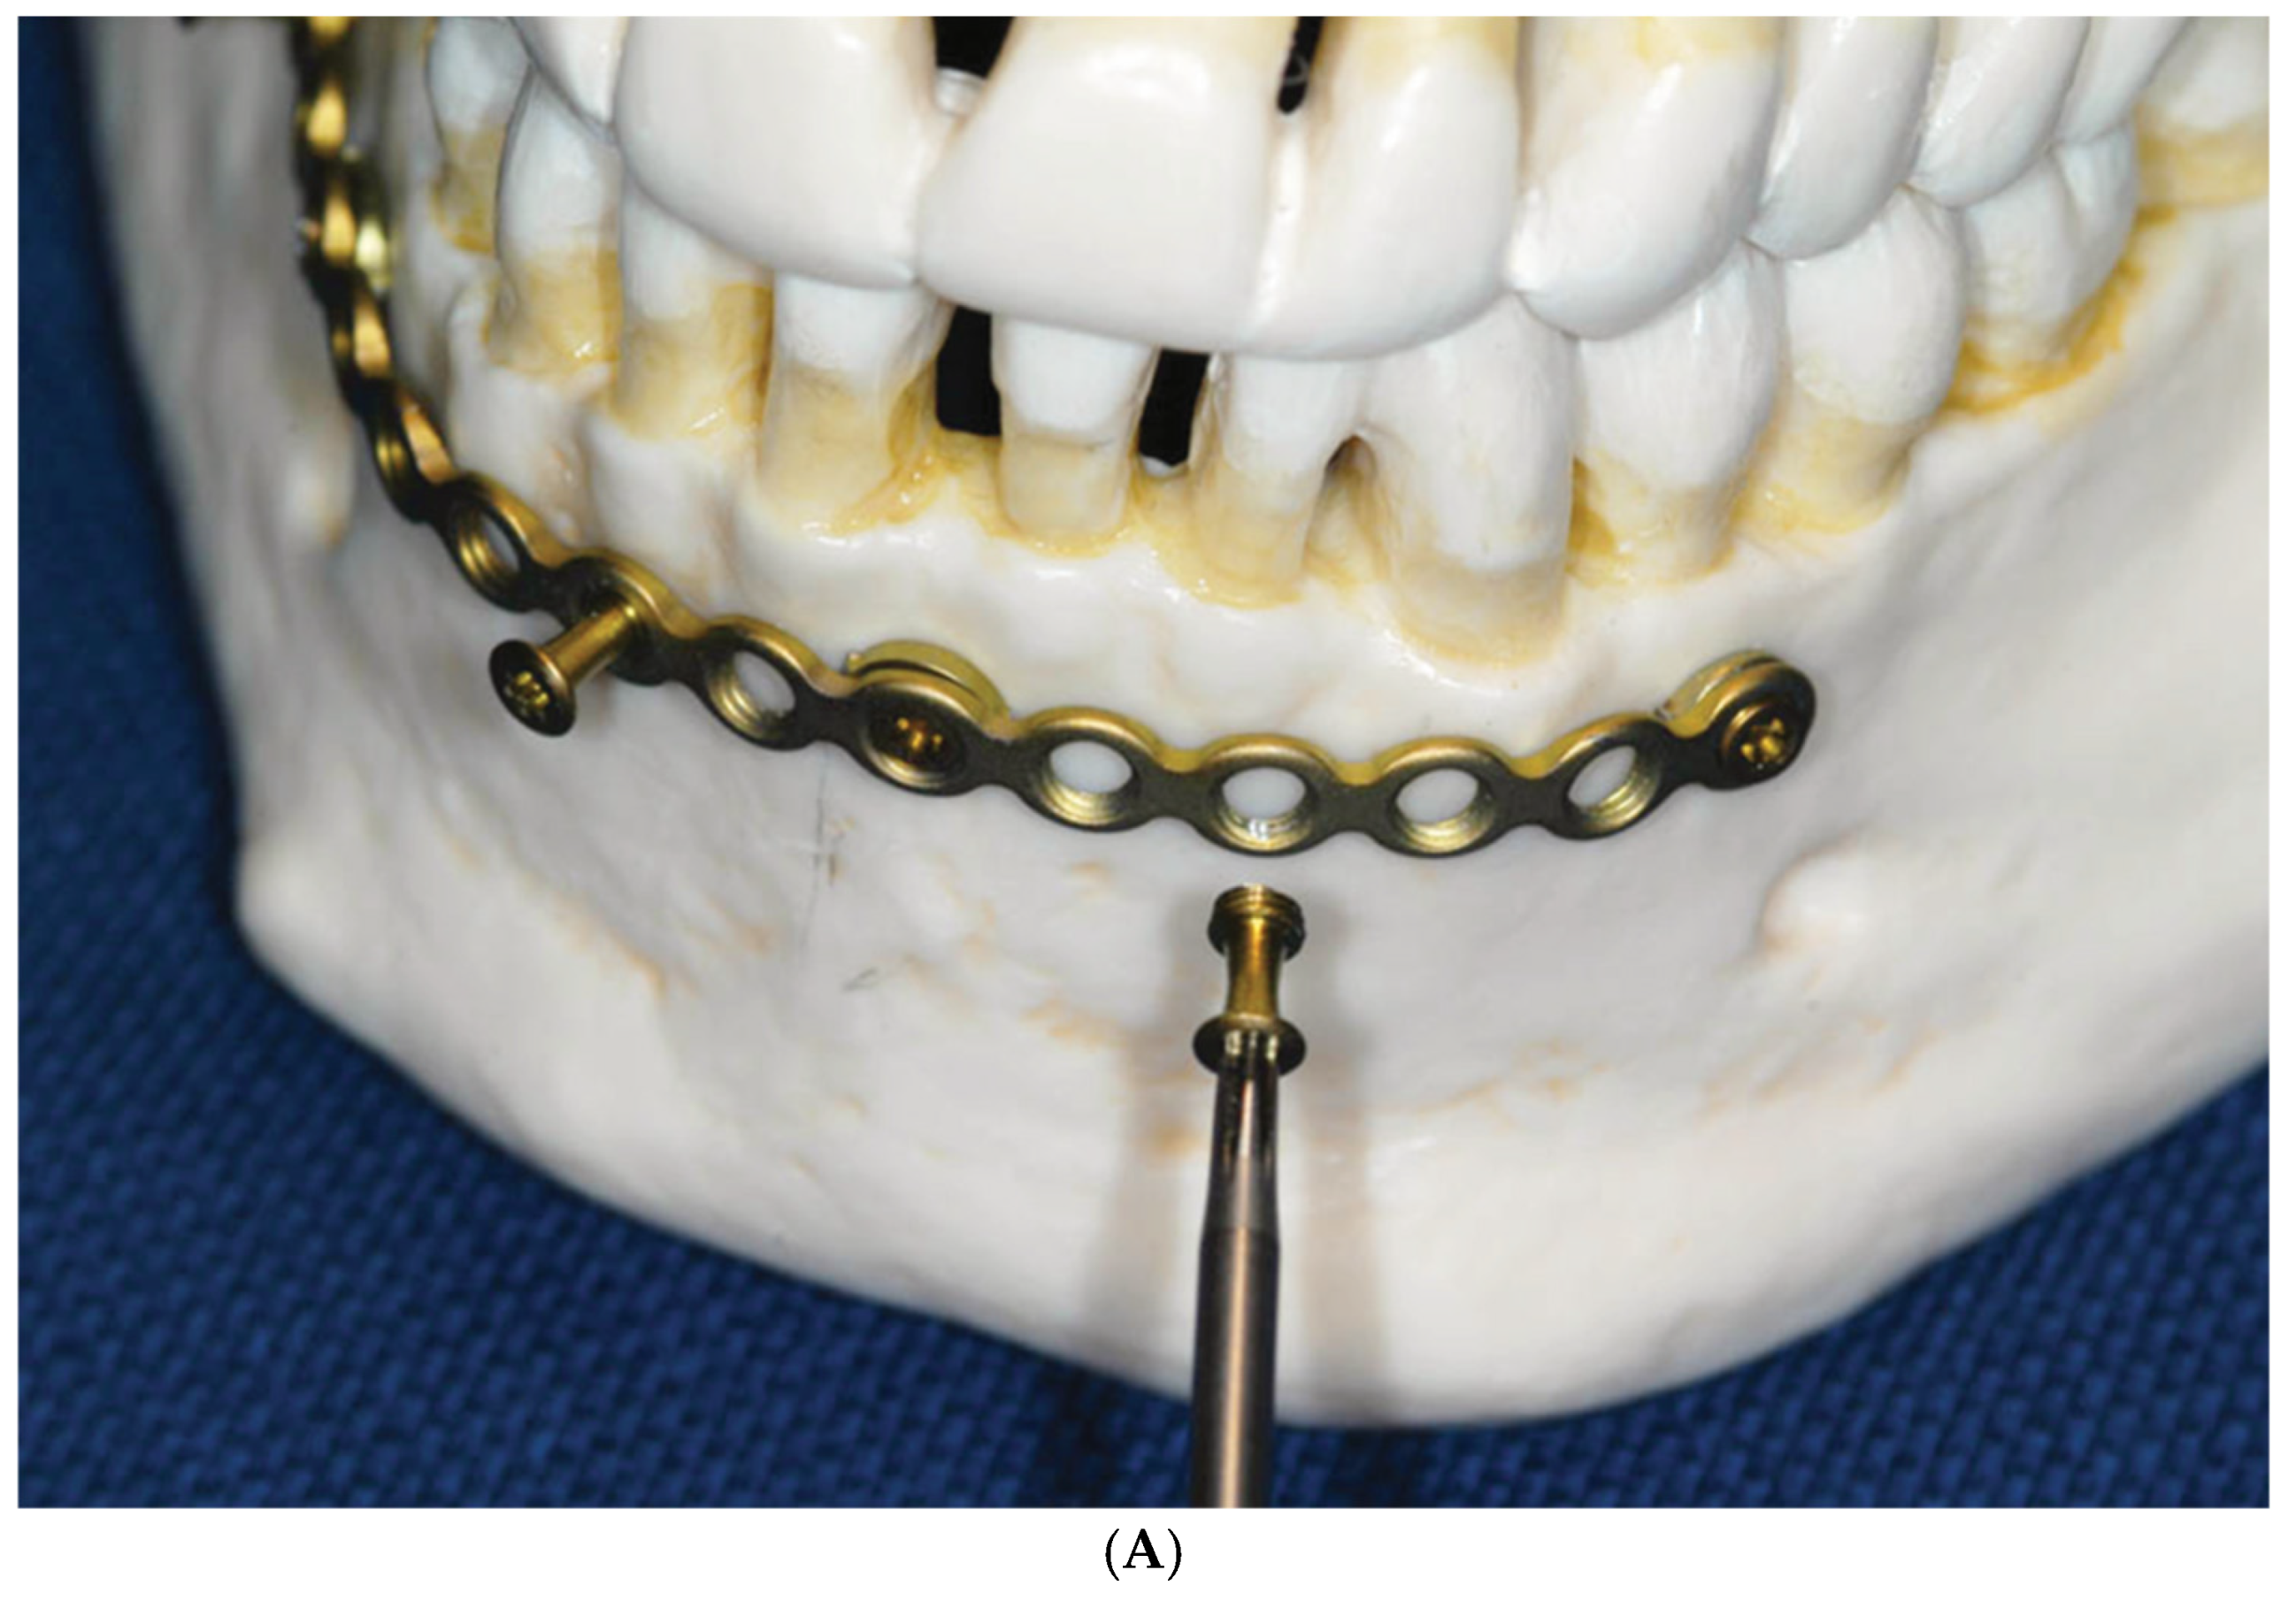

2.1. Locking Adaption Plate and MMF Nuts

2.2. Predecessor—First-Wave Plate Version

2.3. Matrix Wave System—Final Design and Technical Description